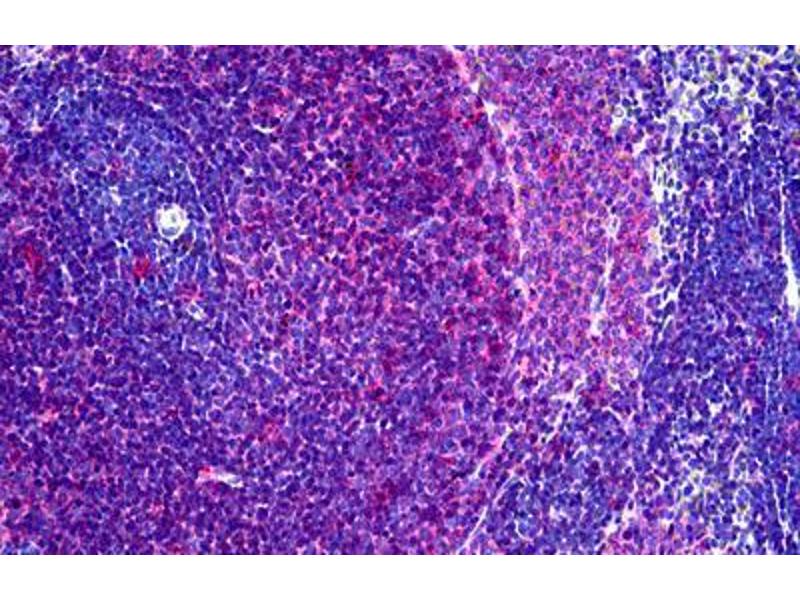

The Mouse Monoclonal anti-MHC Class II RT-1B antibody is suitable to detect MHC Class II RT-1B in samples from Rat and Mouse. It has been validated for FACS, IHC (fro), IHC (p), WB and IHC.

Flow Cytometry (FACS), Immunohistochemistry (Frozen Sections) (IHC (fro)), Immunohistochemistry (Paraffin-embedded Sections) (IHC (p)), Western Blotting (WB), Immunohistochemistry (IHC)

Recognizes a monomorphic determinant of the rat I-A antigen present on B lymphocytes, dendritic cells, some macrophages and certain epithelial cells. Reacts with certain mouse strains of MHC haplotypes k and s. Analysis of recombinant mouse strains showed that the determinants mapped to the I-A region. Does not react with the BDIX rat strain. Expression is polymorphic in mice. This product is routinely tested in flow cytometry on rat splenocytes.

Approved: Flo (1:50 - 1:100), IHC, IHC-Fr, IHC-P (10 μg/mL), WB

Usage: Flow Cytometry: Use 10 μL of the suggested working dilution to label 10^6 cells in 100 μL. Method sheets are available on request. Immunohistology: This product does not require antigen retrieval using heat treatment or protein digestion prior to staining of formalin-fixed paraffin-embedded sections, but results may be enhanced with heat treatment using 0.01M citrate buffer  pH 6.This clone has also been described reacting with paraffin-embedded material following PLP fixation (periodate-lysine-paraformaldehyde)